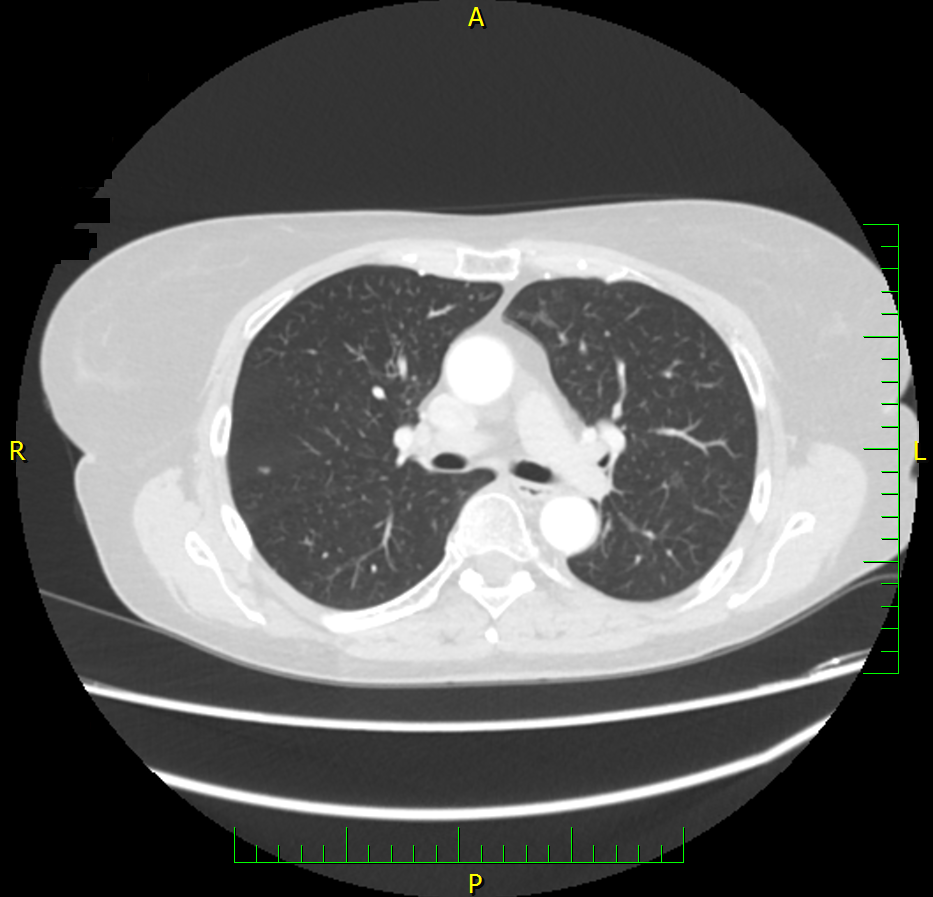

Do vaší ordinace vchází Milan Drahoš. Než se padesátiletý, velmi obézní muž dostane ode dveří k vámi nabízené židli, zadýchá se. Podle CT hrudníku, který si s sebou pacient přináší, má zvětšené uzliny v oblasti mediastina. Snímek odhaluje také mnohočetná ložiska plic. Není na co čekat, je třeba co nejrychleji zahájit léčbu. Ujmete se tohoto případu?